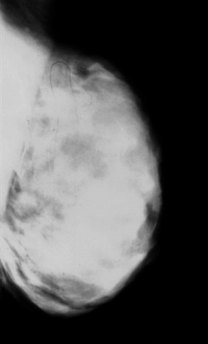

This is an undated handout image

provided on Wednesday, Jan. 17, 2007 by the University of Texas M.D.

Anderson Cancer Center in Houston showing a mammogram of a breast with

dense tissue free of tumors. Dense breast tissue shows up lighter,

obscuring cancer tumors, which also look light on mammograms. The

mammogram of a breast with lots of fatty tissue (the opposite of dense)

appears noticeably darker, so light tumors would show up better against

that background. [AP]

On mammograms, fat looks dark, but

dense tissue is light, like tumors, so it can hide the cancers. But this study

confirms that cancers are also more frequent - not just hidden - in women with

dense breasts.